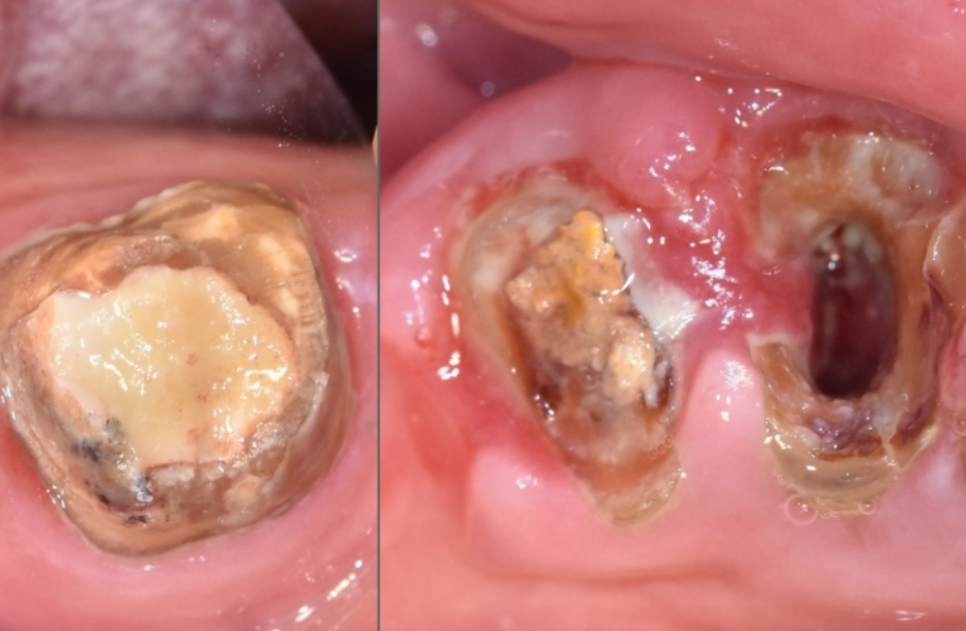

입안을 들여다보니...

오랜 기간 잇몸 관리가 안 되어

주변은 퉁퉁 부어 피가 나는 상태였고,

250507

무엇보다 브릿지를 지탱하던

앞 치아(#43)는

과도한 힘을 버티지 못하고

치아 반쪽이 깨져 있었습니다.

맨 끝 치아(#47) 역시 뿌리 끝에

고름주머니가 크게 잡혀 있었죠.